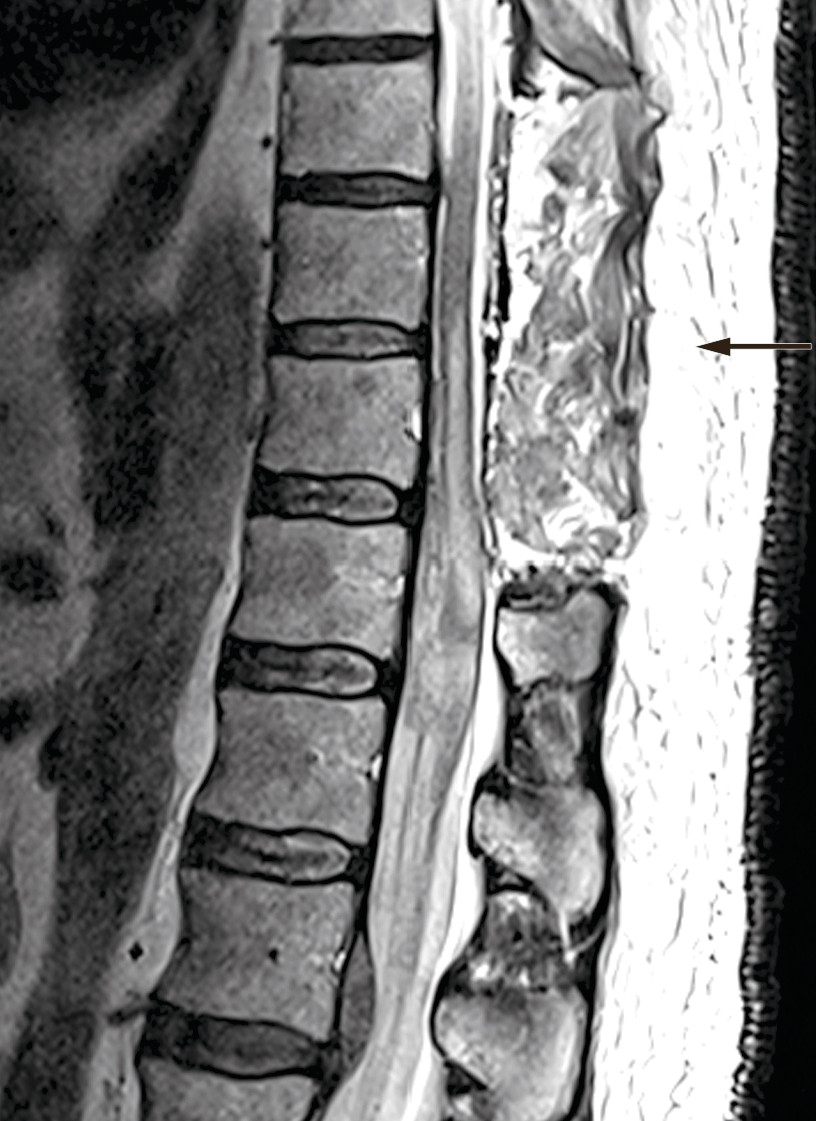

Pasienten ble meldt til akutt operasjon i narkose. Det ble brukt kne- og albueleie, røntgengjennomlysning, midtlinjesnitt og laminektomi i tre nivåer. Peroperativt var det ikke noe epiduralt hematom, men blå, misfarget dura mater ble åpnet. Det ble skånsomt evakuert subduralt hematom, og det var ingen stor blødningskilde eller vansker med å oppnå hemostase. Ryggmargen var blålig misfarget, og en mistenkte betydelig blødning subaraknoidalt og intramedullært. Det ble da utført lukning under god hemostase. Postoperativ MR-undersøkelse viste volumredusert subduralt hematom i laminektomert nivå Th9–11, uendret subduralt hematom i nivå Th12, tilkomne intramedullære signalforandringer i nivå Th10–L1 og subaraknoidalt blod kaudalt for Th12 (figur 2).